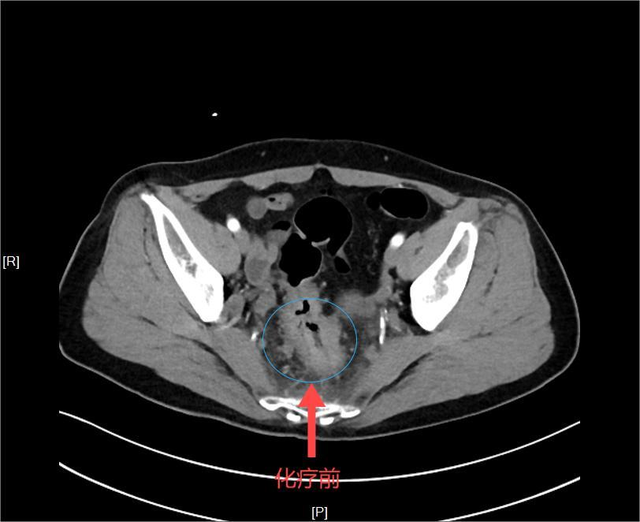

令人欣慰的是,经过四次两疗程的转化治疗后,刘阿姨明显感觉下腹部好像少了一样东西,身体轻松了好多。经过再次的增强CT评估,发现直肠肿瘤瘤体明显缩小,CT上几乎不可见,转移的淋巴结也明显缩小,显示出理想的治疗效果。

▲化疗前